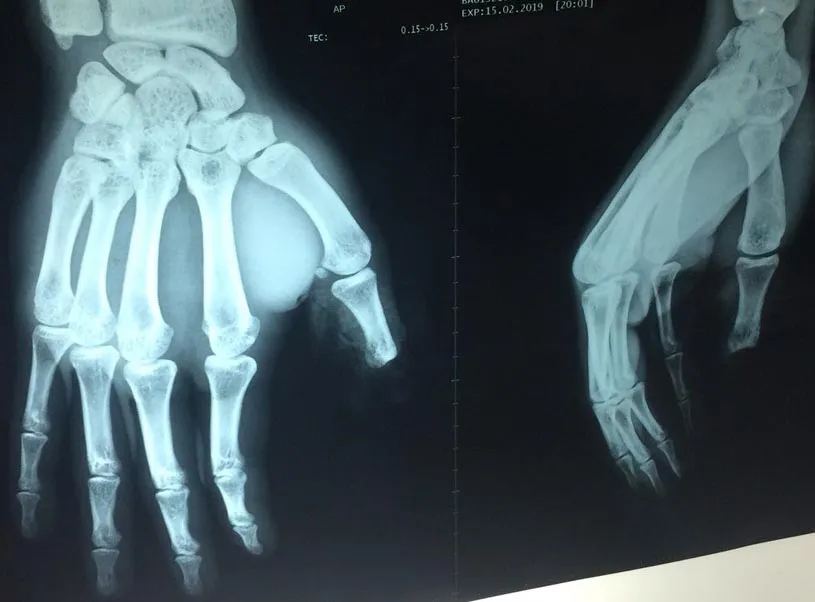

Kết quả chụp X quang cho thấy một đốt ngón tay cái anh Đ. bị đứt rời. Ảnh: HÒA KHÁNH